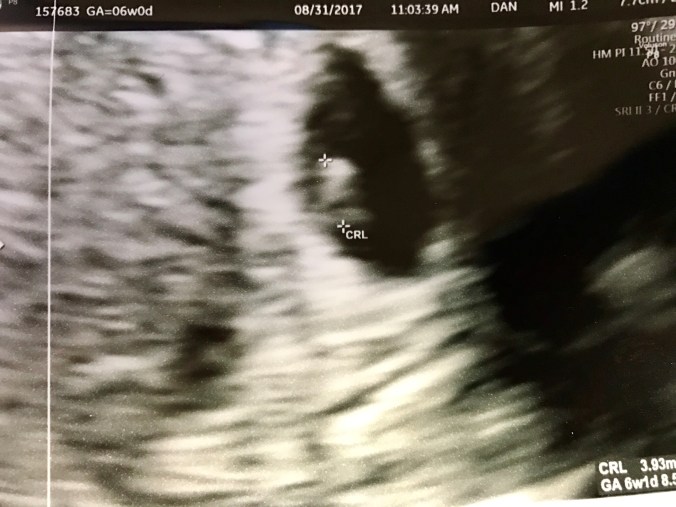

“Well, it’s something,” the tech said. “Let’s keep going.” She moved the probe around a bit, and suddenly, I gasped. There, right there on the screen, was a definite gestational sac with everything in place–the yolk sac, which provides nutrients for the baby until the placenta is fully developed, and the fetal pole, the beginnings of the baby itself. And flickering right there, in the middle of the fetal pole, was a heartbeat. Constant. Steady. And faster than we’d seen since Sam.

“98 beats per minute, which is excellent at this stage!” the tech announced. Faster than it had ever been with our first miscarriage last year. Steady. Strong.

(the legume in question, measuring exactly six weeks, one day)